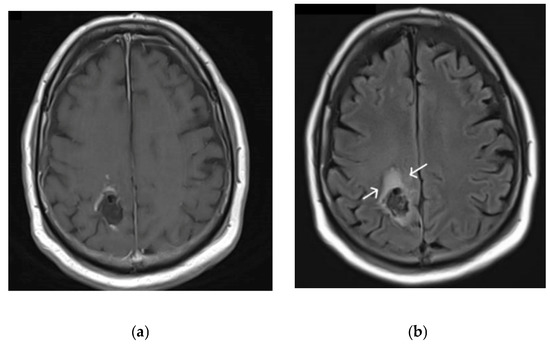

- Coburger, J.; Engelke, J.; Scheuerle, A.; Thal, D.; Hlavac, M.; Wirtz, C.R.; König, R. Tumor detection with 5-aminolevulinic acid fluorescence and Gd-DTPA–Enhanced intraoperative MRI at the border of contrast-enhancing lesions: A prospective study based on histopathological assessment. Neurosurg. Focus 2014, 36, E3. [Google Scholar] [CrossRef]

- Roberts, D.W.; Valdés, P.A.; Harris, B.T.; Fontaine, K.M.; Hartov, A.; Fan, X.; Ji, S.; Lollis, S.S.; Pogue, B.; Leblond, F.; et al. Coregistered fluorescence-enhanced tumor resection of malignant glioma: Relationships between δ-aminolevulinic acid–induced protoporphyrin IX fluorescence, magnetic resonance imaging enhancement, and neuropathological parameters. J. Neurosurg. 2011, 114, 595–603. [Google Scholar] [CrossRef]

- Stummer, W.; Tonn, J.-C.; Goetz, C.; Ullrich, W.; Stepp, H.; Bink, A.; Pietsch, T.; Pichlmeier, U. 5-Aminolevulinic Acid-derived Tumor Fluorescence: The Diagnostic Accuracy of Visible Fluorescence Qualities as Corroborated by Spectrometry and Histology and Postoperative Imaging. Neurosurgery 2013, 74, 310–320. [Google Scholar] [CrossRef] [PubMed]